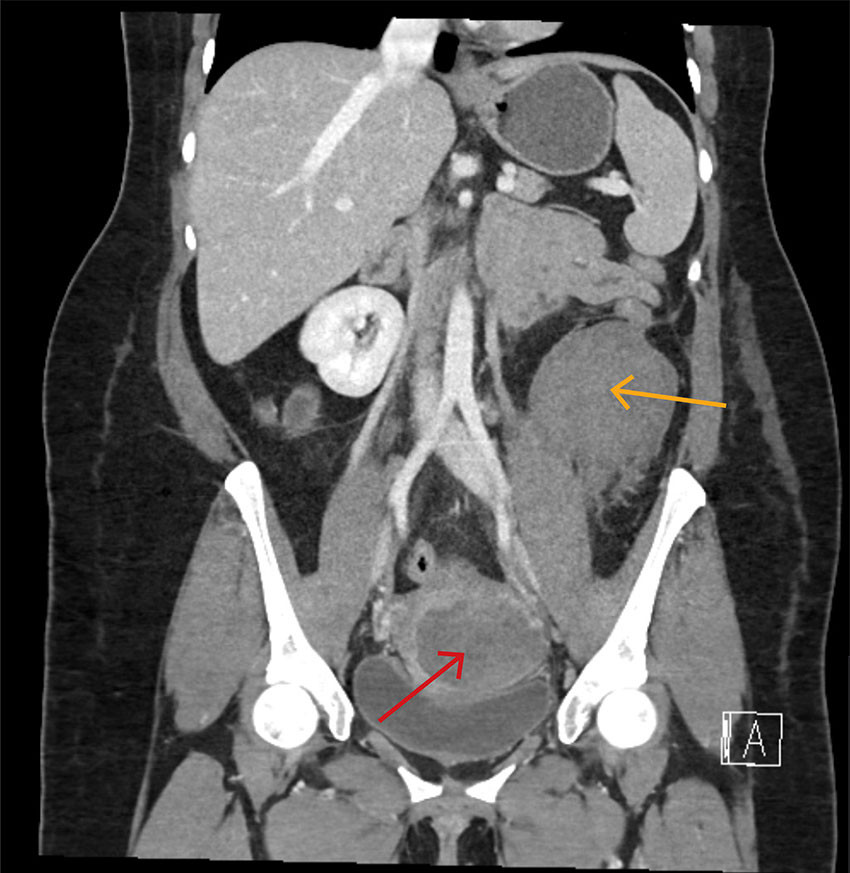

Åtte dager postpartum begynte pasienten plutselig å blø rikelig vaginalt. Ambulansepersonell mistenkte alvorlig blødning med estimert mengde på 2–3 L, og bestilte kriseblod. Blodtrykk lå mellom 56/34 og 101/66 mmHg, og puls var 135 per minutt. Hun ble oppfattet som hemodynamisk ustabil, og grunnet værforhold ble hun fløyet til et universitetssykehus med luftambulansehelikopter istedenfor til fødesykehuset. Under transporten var pasienten våken, og blodtrykket ble målt fire ganger til rundt 110/70 mmHg, pulsen gradvis fallende til 126 per minutt. Det ble gitt en pose RhD-positivt blod, en pakke LyoPlas (frysetørret plasma), og traneksamsyre 2 g intravenøst. Hun ble møtt av kirurgisk mottaksteam på universitetssykehuset. Det var normalt blodtrykk, puls 108 per minutt og ingen pågående vaginalblødning. Ultralyd abdomen viste ingen fri væske. CT avdekket et stort retroperitonealt hematom med mistenkt aktiv blødning og et mindre hematom i cervix/vagina (figur 3). Bildene fra fødselsinnleggelsen ble gransket på nytt, og man så for første gang at hematomet som var beskrevet som intraperitonealt ved fødesykehuset, også da hovedsakelig lå retroperitonealt.

Vår pasient hadde alvorlige symptomer som kunne stamme fra flere organsystemer. En bred tilnærming var derfor viktig for å finne riktig diagnose. En intensivseng er på sitt beste en perfekt plass for et slikt kollokvium. Det viste seg at pasienten hadde blødningssjokk forårsaket av uterusruptur med både uvanlig presentasjon og lokalisasjon av påfølgende hematom. Sammen med en initial tolkning av hematomet som intraperitonealt bidro dette til å forsinke diagnosen. CT ble først protokollert og utført uten intravenøs kontrast, noe som riktignok påviste blødning, men som vanskeliggjorde vurdering av lokalisasjon og omfang av dette. Påfølgende serier med intravenøs kontrast ble ikke gjort da pasienten ble oppfattet som sirkulatorisk ustabil og tatt rett til operasjon. Som hovedregel bør pasienter som man mistenker har pågående blødning eller sirkulatorisk sjokk, få utført flerfaset CT med intravenøs kontrast, med eller uten «tomserie».

Ved første inngrep trodde behandlingsteamet at man hadde funnet forklarende årsak på pasientens tilstand med uterusruptur og intraperitonealt hematom med pågående blødning. Det viste seg imidlertid at det også forelå et stort retroperitonealt hematom. Dette forklarer at mengden koagler ved primærinngrepet ble oppfattet som noe mindre enn forventet, og at pasienten hadde et stort transfusjonsbehov. Retroperitoneale hematomer er primært en radiologisk diagnose, og vil ikke kunne avdekkes ved intraperitoneal laparotomi via Pfannenstiel-snitt (11). Dette understreker viktigheten av å lete videre dersom kart og terreng ikke passer helt. Misoppfattelsen av hematomets beliggenhet ved fødesykehuset og antagelsen om en pågående blødning ved universitetssykehuset, kan ha ført til en unødvendig ekstra laparotomi. På universitetssykehuset ble kirurgisk mottaksteam aktivert på grunn av ambulansepersonellets bekymringsfulle observasjoner. Med mange involverte i et hektisk miljø, er alle innstilt på å sikre rask og effektiv behandling, som ofte er kirurgi. I en slik kontekst kan det være utfordrende å stoppe opp og bruke den tiden som trengs for å konstatere at pasientens tilstand likevel ikke krever det.

Som pasientkasustikken viser, er det slik at den i ettertid perfekte tilnærmingen i praksis ofte ikke gjøres. Vi ønsker å fremheve tre hovedlæringspunkter fra pasientforløpet. Det er viktig å være bevisst på at retroperitoneale hematomer kan oppstå hos fødende (11). Ved uterusruptur kan blod dissekere seg opp langs ligamentum latum og videre inn i retroperitoneum, og gi blødningssjokk uten større forutgående symptomer (13, 14). Et annet læringspunkt er at det kan være utfordrende radiologisk å skille mellom intra- og retroperitonealt hematom, og å avklare om det er billedmessige tegn til pågående blødning. Dette fordrer ekstra årvåkenhet fra kirurger når radiologiske og kliniske funn ikke helt samsvarer. Om enn mindre unikt, er det siste læringspunktet viktigheten av god kommunikasjon og samhandling i den akuttmedisinske kjeden for å sikre rask og god behandling.